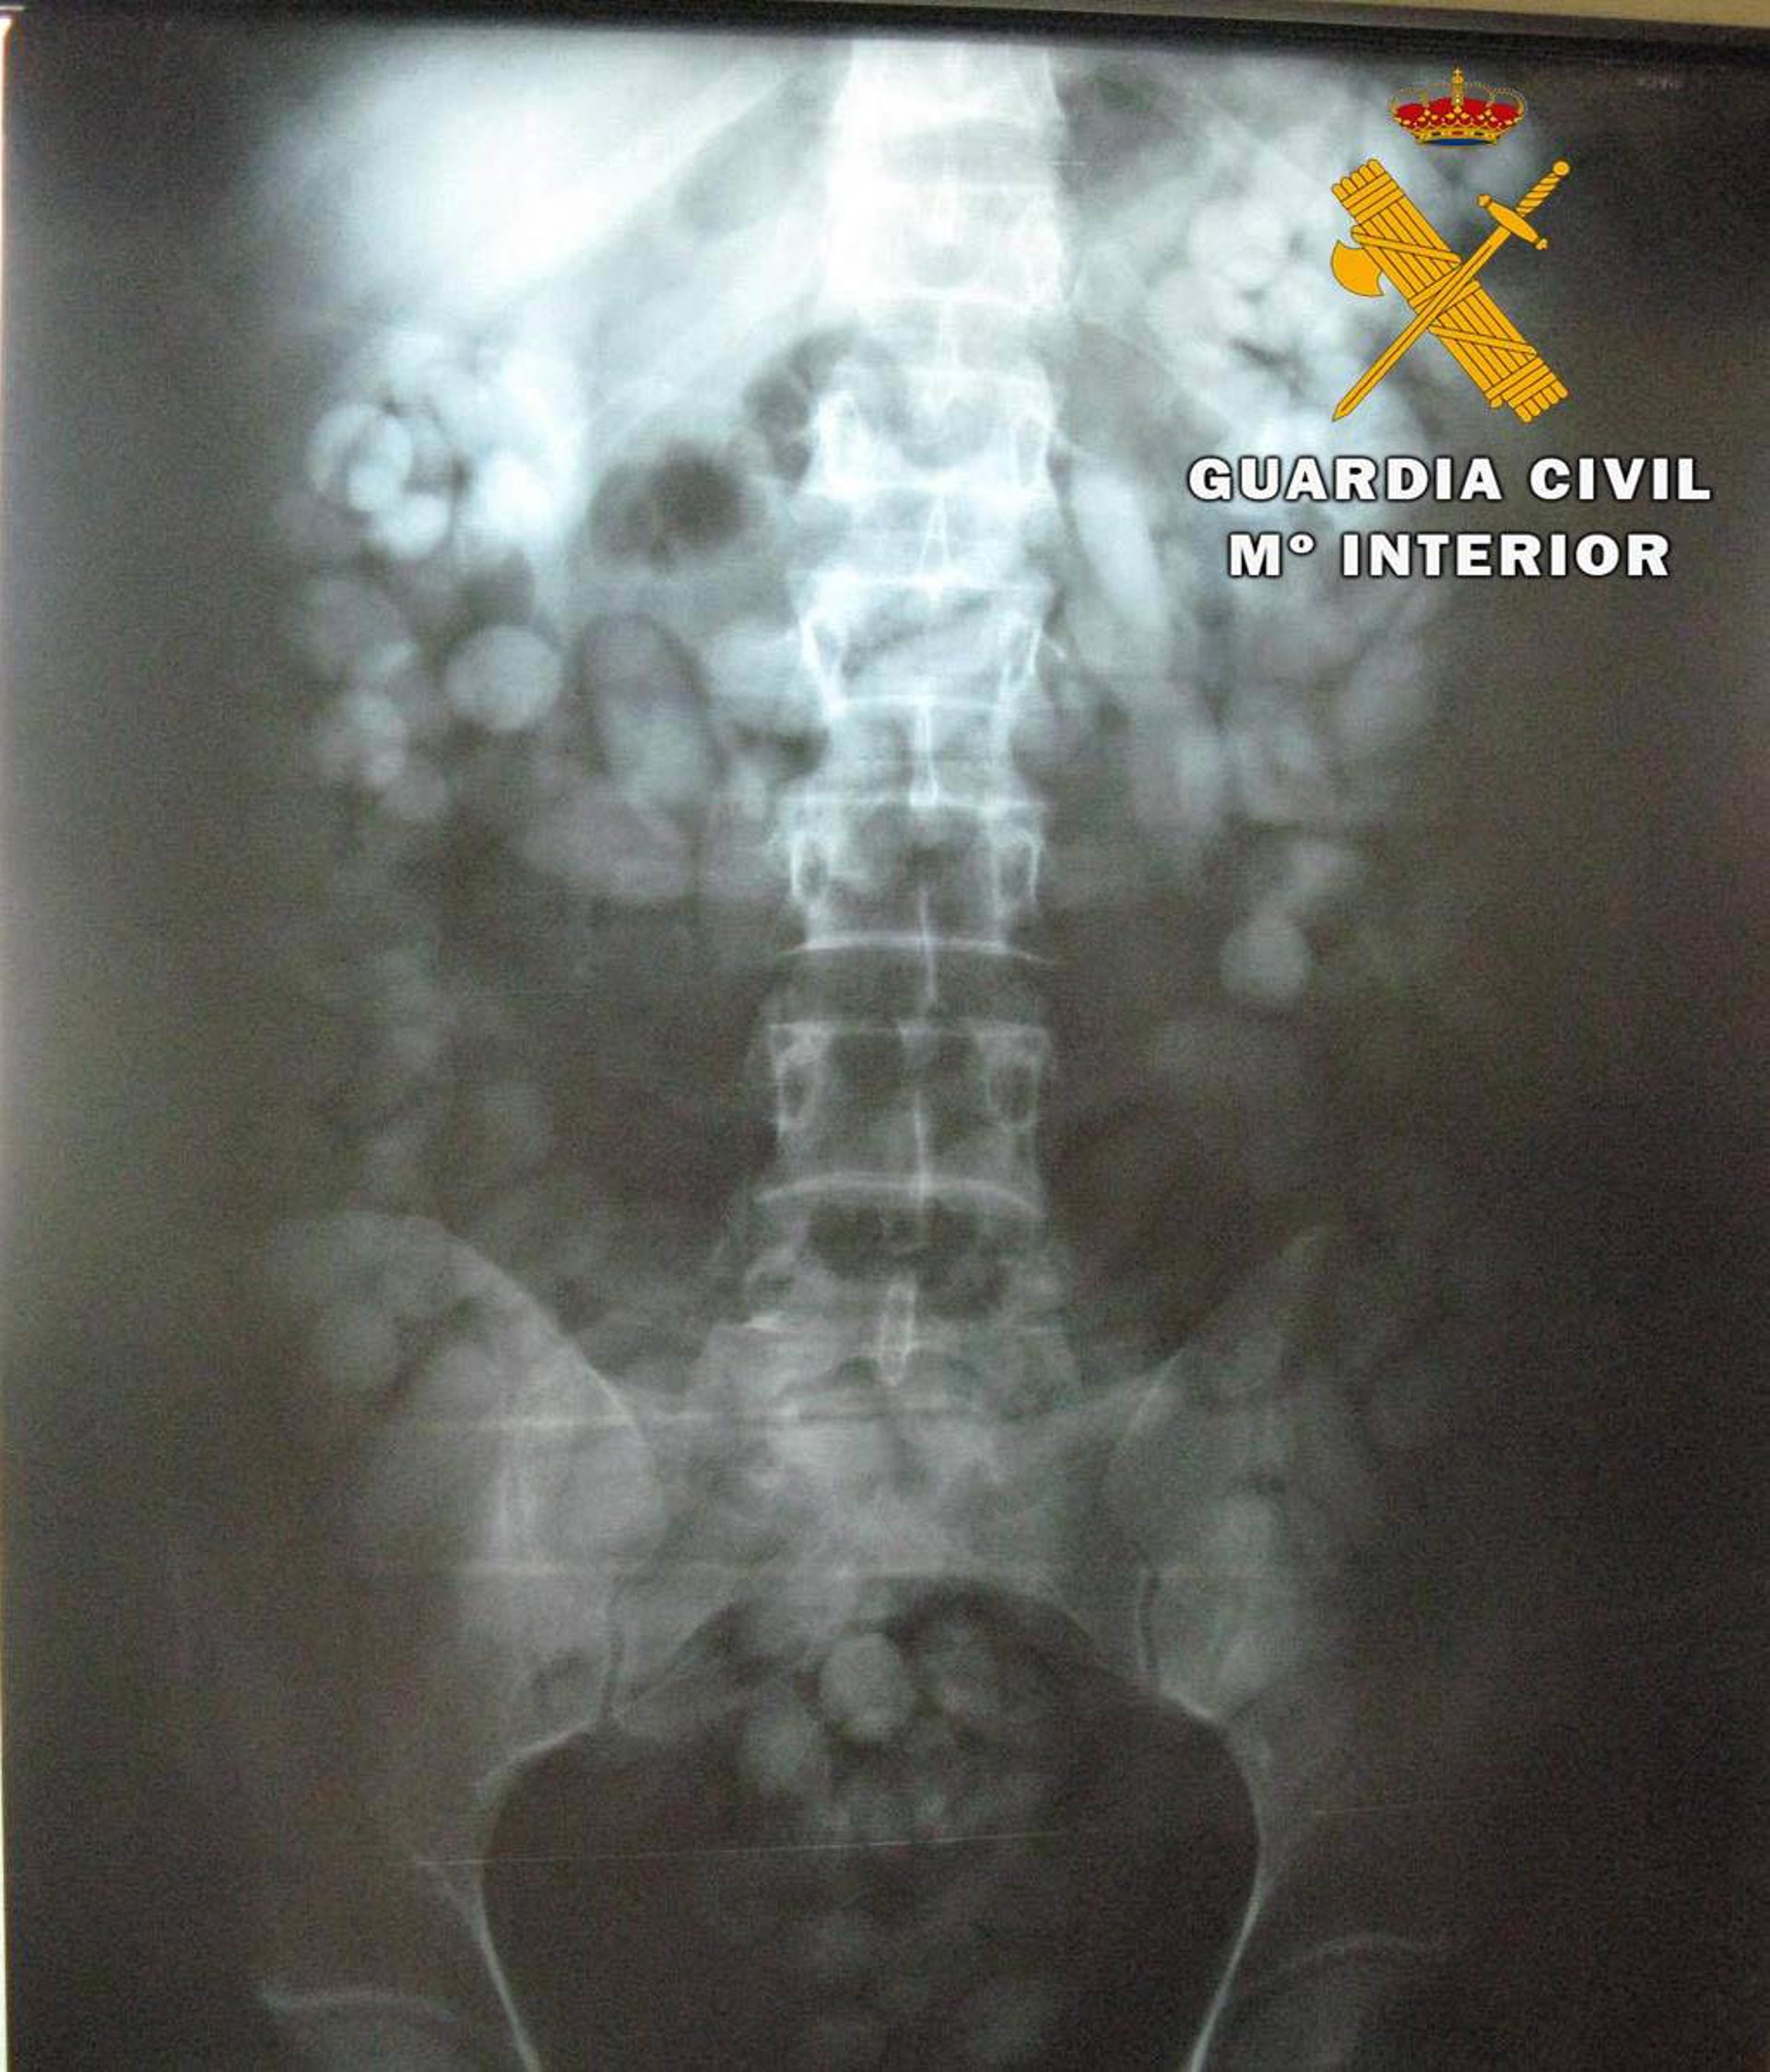

Según ha indicado la Guardia Civil, presentaba evidentes síntomas de nerviosismo y sudoración ante la presencia policial, por lo que, tras inspeccionar su equipaje de mano, se le instó a someterse de forma voluntaria una prueba de exploración radiológica del abdomen en el Hospital de Alta Resolución de El Toyo de Almería.

Tras ser sometido a la exploración radiológica, se detectaron numerosos cuerpos extraños en el interior del aparato digestivo de esta persona, siendo expulsados más tarde y dando un total de 216 bellotas con un peso de 1,511 kilos de hachís.